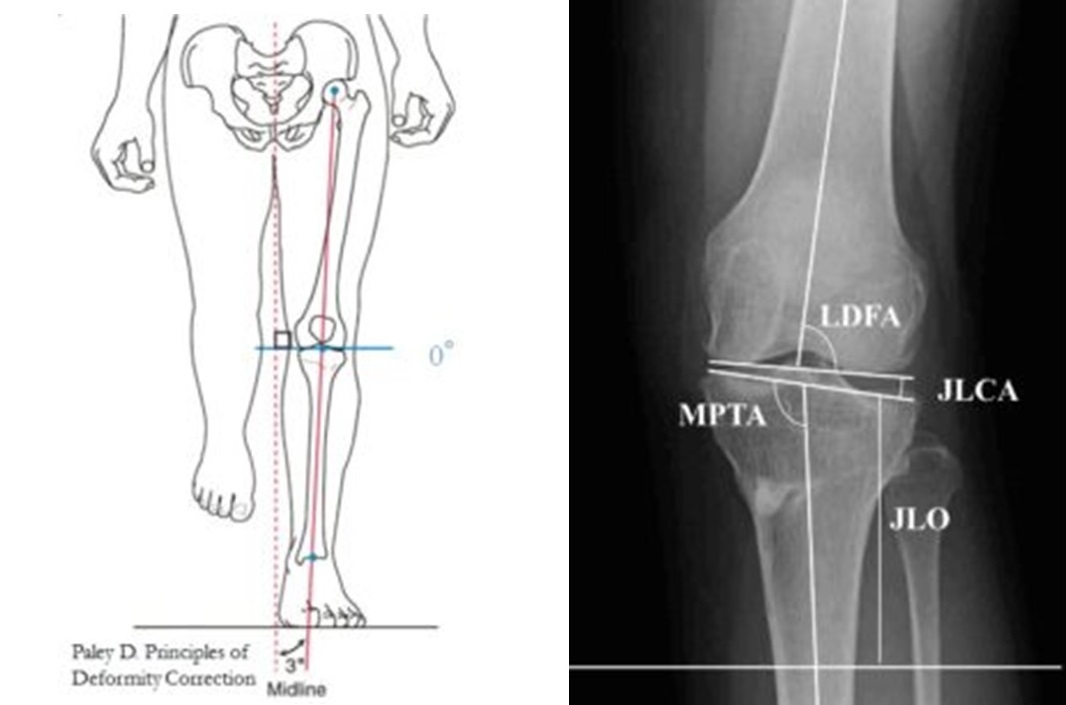

片足で立った時の膝関節面を地面に平行にします。

正常人の膝は片足で立ったとき、関節線が地面に対し平行になるのが原則です。ただし、それがどの程度の活動性、年齢の方まで必要なのかは、今後の課題です。

左図青線:片足立ちで関節面が平行。右図:関節が傾向いている。

JLO (Joint line obliquity=片脚で立った時の脛骨関節面の地面に対する角度)は術後MPTAを95°以下で計画し手術をすると 手術後3°と地面に対しより平行になりました。KOOS (Knee injury and Osteoarthritis Outcome Score) スコアーのスポーツ&レクリエーションの項目で 近位脛骨内側角 (MPTA)が95°以下群の成績が良好でした。

左図:MPTAが95°以下群の成績が良好でした。右図:MPTAが95°超える群ではJLOは地面に対しより傾き、スポーツスコアーも劣っていました。

しかし、高位脛骨骨切り術をおこなうと関節面傾斜角が増加します。

この傾きは何度までが限界なのかはっきりしません。

そこで、関節面傾斜角を増加させる最大の因子である近位脛骨内側角(MPTA)が95°以下と95°超える群での成績を調査し英文誌に報告しました。